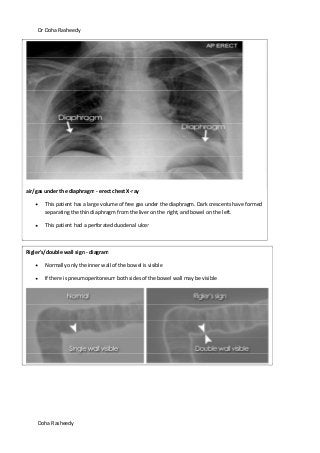

air/gas under the diaphragm - erect chest X-ray

This patient has a large volume of free gas under the diaphragm. Dark crescents have formed

separating the thin diaphragm from the liver on the right, and bowel on the left.

This patient had a perforated duodenal ulcer

Rigler's/double wall sign - diagram

Normally only the inner wall of the bowel is visible

If there is pneumoperitoneum both sides of the bowel wall may be visible